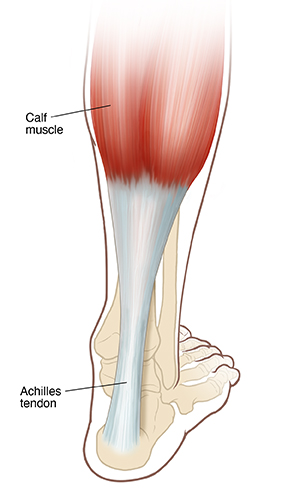

The Achilles tendon is a strong, fibrous cord in the back of your lower leg. It connects the muscles of your calf to your heel. It’s the largest tendon in your body. It helps you walk, run, and jump. Achilles tendon repair surgery is a type of surgery to fix a damaged Achilles tendon. The damage may be a tear or rupture from a sudden (acute) injury. Or the damage may be from overuse, or wear and tear, or from other conditions. This long-term (chronic) injury is also known as tendonitis or tendinopathy.